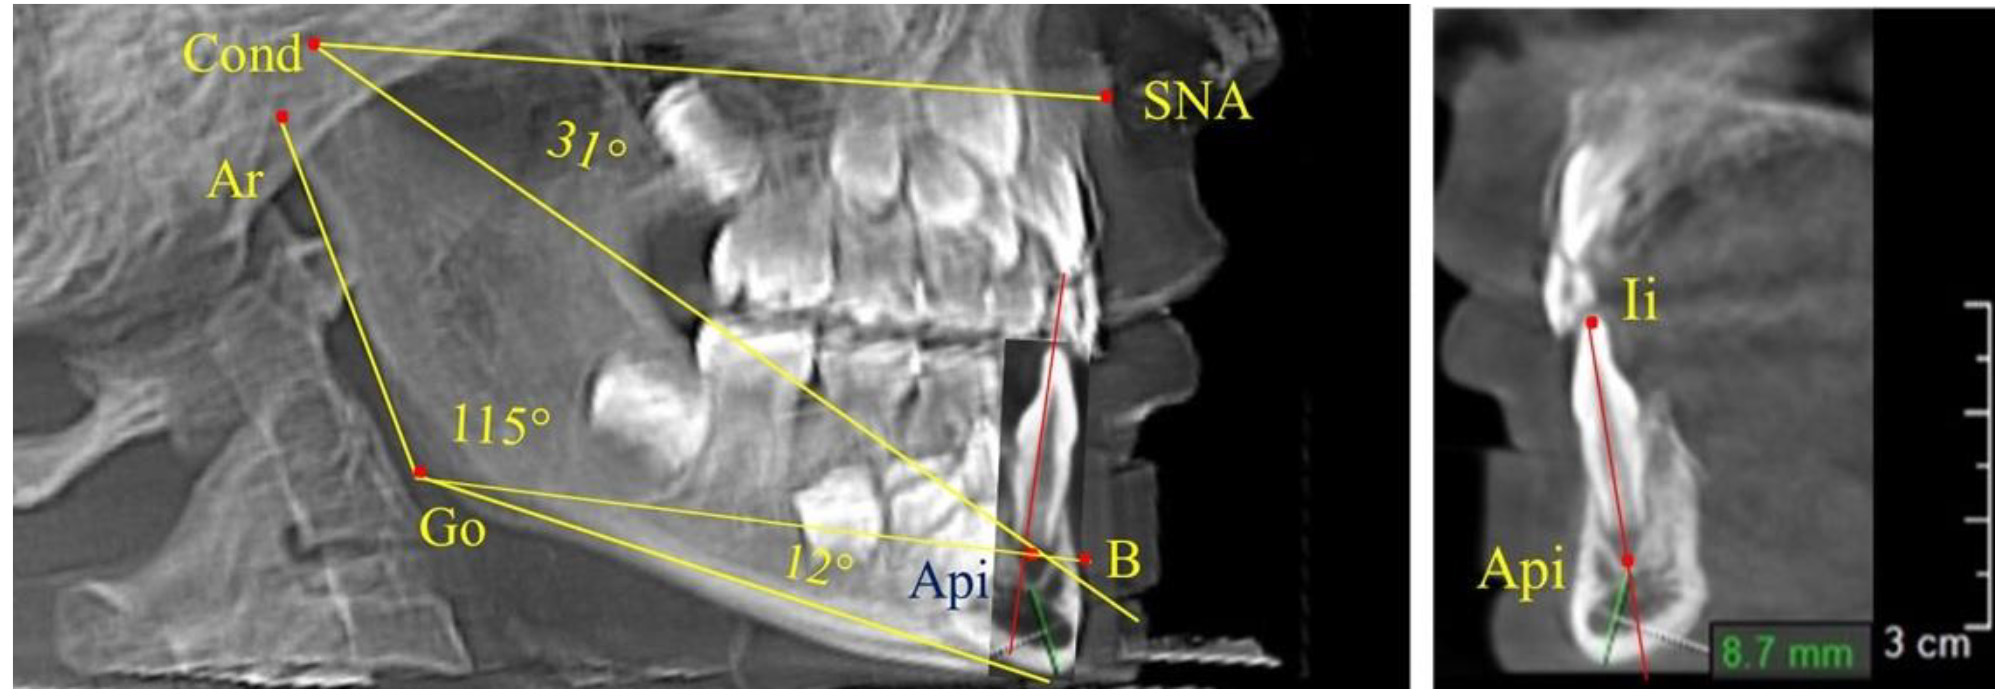

Особенность анализа телерентгенограммы в периоде сменного прикуса заключалась в том, что наслоение зачатков постоянных зубов затрудняло определение апикальной точки нижнего резца. В подобных случаях использовали метод совмещенного анализа телерентгенограммы с фрагментом томограммы, на котором, также как и на телерентгенограмме, определяли положение резцовой и апикальной точек с построением условной вертикали, которая служила ориентиром для совмещения фрагментов (рис. 2).

Рис. 2. Особенности совмещения телерентгенограммы с фрагментом томограммы в сменном прикусе

После смены всех молочных зубов (анализ 9 ТРГ) и после прорезывания вторых постоянных моляров (7 человек) происходил очередной этап подъема высоты прикуса с увеличением размеров костей гнатической части лица. Однако величина основного угла гнатической части лица SNA-Cond-Api, так же как в молочном и сменном прикусе, в норме составляла (30,02 ± 1,25)°, что не имело достоверных различий (р ˃ 0,05) с аналогичным параметром, анализируемом в других группах исследования. Угол нижней челюсти и его составляющие отличались вариабельностью параметров при различных показателях нижнечелюстного угла (рис. 6).

Рис. 6. Варианты 3D рентгенограмм детей после смены всех молочных зубов (а) и после прорезывания вторых моляров (б)